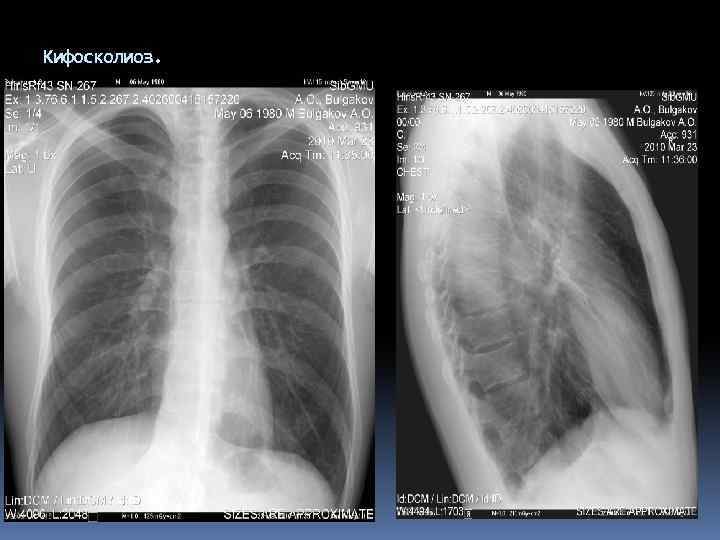

Кифосколиоз.